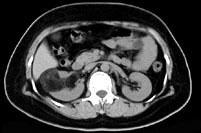

问题 男,55岁,因右腰部不适1 年余,行CT扫描如图所示,下列说法正确的是 ( )

选项 A、考虑为右肾癌 B、考虑为右肾错构瘤 C、其内见低密度脂肪影 D、其边缘清楚,与周围境界清晰 E、右肾中极可见一类圆形肿块影,肿块密度不均

答案 BCDE